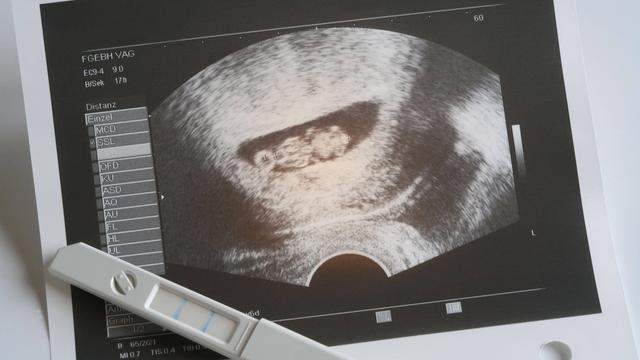

Der Herzschlag des Fetus kann ab der 5. Schwangerschaftswoche (SSW) im Ultraschall festgestellt werden. In dieser Zeit beginnt das Herz zu schlagen und der Herzschlag ist bereits ab der 6. Woche auf dem Ultraschall sichtbar. Der Herzschlag wird als ein wichtiger Meilenstein in der frühen Schwangerschaft angesehen, da er darauf hinweist, dass die Entwicklung des Embryos gut verläuft.

Weitere Informationen zum Herzschlag des Fetus:

– Der Herzschlag des Fetus wird normalerweise zwischen 120 und 160 Mal pro Minute gemessen.

– Das Überwachen des Herzschlags während der Schwangerschaft ist wichtig, um sicherzustellen, dass das Baby gesund ist und sich normal entwickelt.

– Der Herzschlag kann mit Hilfe eines vaginalen Ultraschalls oder eines Bauchultraschalls festgestellt werden.

– Das Vorhandensein eines regelmäßigen und starken Herzschlags ist ein positives Zeichen für eine gesunde Schwangerschaft.